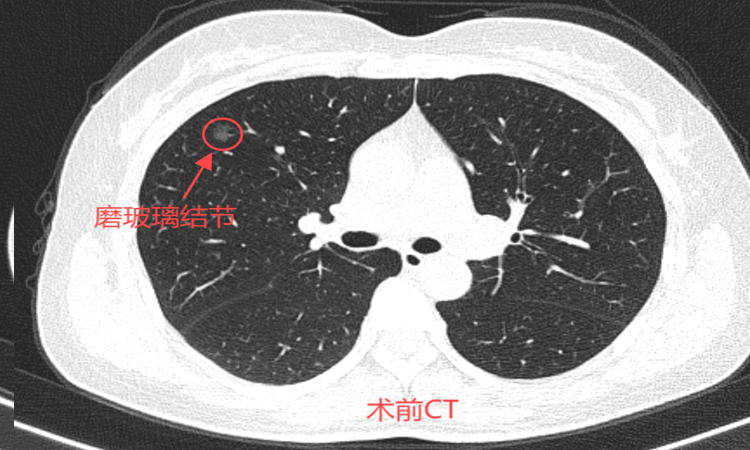

46岁的孙女士一年前在一次偶然的体检中发现自己双肺有多发磨玻璃结节。在医生的建议下,决定先进行随访,等结节有变化了再做处理。今年复查时发现最大结节已经达0.9*0.8cm,因担心癌变可能,于近日前往北京某三甲医院就诊,看诊后专家建议行消融治疗,经过多方咨询后就诊于我院。

患者术前肺多发磨玻璃结节